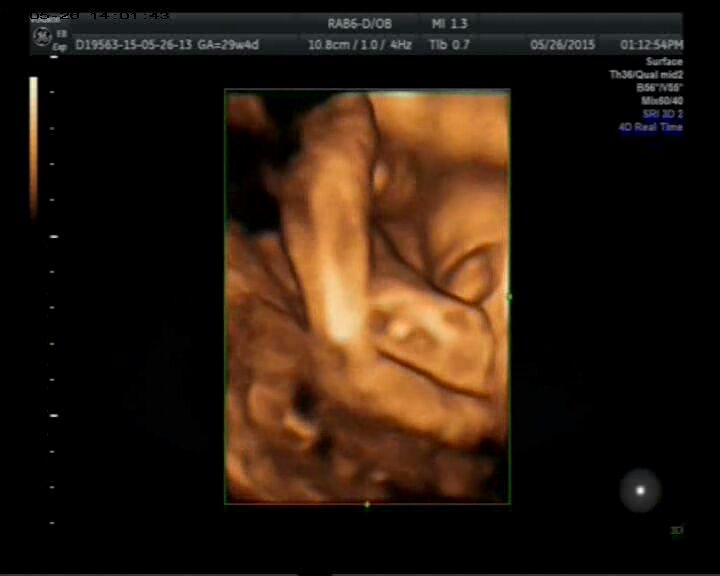

四维照片是男孩还是女孩? 点击展开 匿名用户 2015-06-12 10:34 推荐回答 分明是女孩。你是豆指不是已经知道了孩子的性别?根据宝宝的姿司药唤势和面部表情判断的,说不出理由,只是苦毫经验。 匿名用户 2015-06-25 09:21 宝宝知道提示您:回答为网友贡献,仅供参考。 为您推荐: 其他回答 女孩 脱俊能_7Gn7 2015-06-12 11:30 这个看不出来呢 匿名用户 2015-06-12 10:52 在 匿名用户 2015-06-12 10:38 相关问题 看看我的四维彩超是男孩还是女孩 我怀孕快六个月了,前天做的四维彩超,心率一分钟是139,请问是男孩还是女孩啊 有懂的吗?帮忙看下四维宝宝是男孩还是女孩 听说面朝左边是男孩 我家是面朝右的吗?